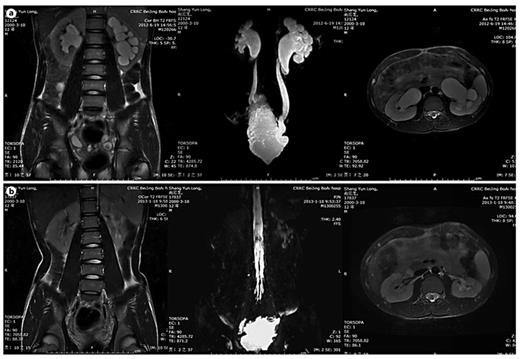

Improvement of UUTD grades by MRU after 6 months of augmentation enterocystoplasty. a Preoperative UUTD grades of right and left kidneys were 3 and 4, respectively. b Postoperative UUTD grades of right and left kidneys became 0 and 1, respectively. A significant improvement is shown.